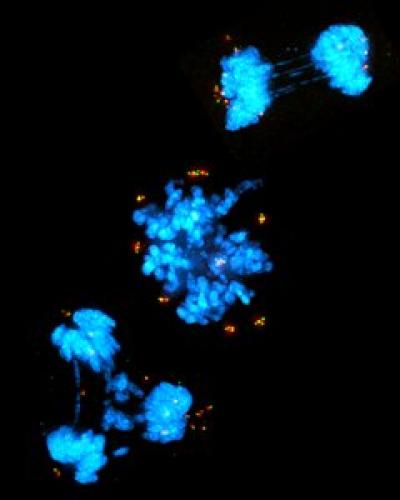

During their search, he says, they came across a line of human breast cancer cells that are very dependent on cell structures called centrioles to divide and survive. Centrioles act as the structural core of centrosomes, which organize thin tubes of proteins that give cells their shape and help separate DNA when the cell divides. However, many cells can divide without centrioles and centrosomes.

Although other cells are able to live without centrioles, Holland's team found that these lab-grown breast cancer cells could not.

Close analysis showed that the centriole-dependent breast cancer cells had a section of genome that had been abnormally copied many times, an alteration found in about 9% of breast cancers. The researchers studied the genes encoded in the highly copied region and found a gene that was producing high levels of a protein -- TRIM37 -- shown to control centrosomes.

Next, the researchers tested a way to interfere with the cell division process in the cells with high TRIM37 levels. They used an experimental drug called a PLK4 inhibitor, which disrupts proteins that make centrioles. They added the drug to the lab-grown breast cancer cells with normal TRIM37 levels and found that the cells were able to successfully divide, even though the drug had removed the cell's centrioles.

However, when they added the drug to breast cancer cells with high TRIM37 levels, the opposite happened -- the cells could no longer divide and most cells stopped growing or died.

In the current study, the researchers found that high levels of TRIM37 cause cells to degrade pericentriolar material. Thus, by adding a drug that removes centrioles, the cells have no way -- either with centrosomes or pericentriolar material -- to organize the tubes that help divide the DNA during cell division.